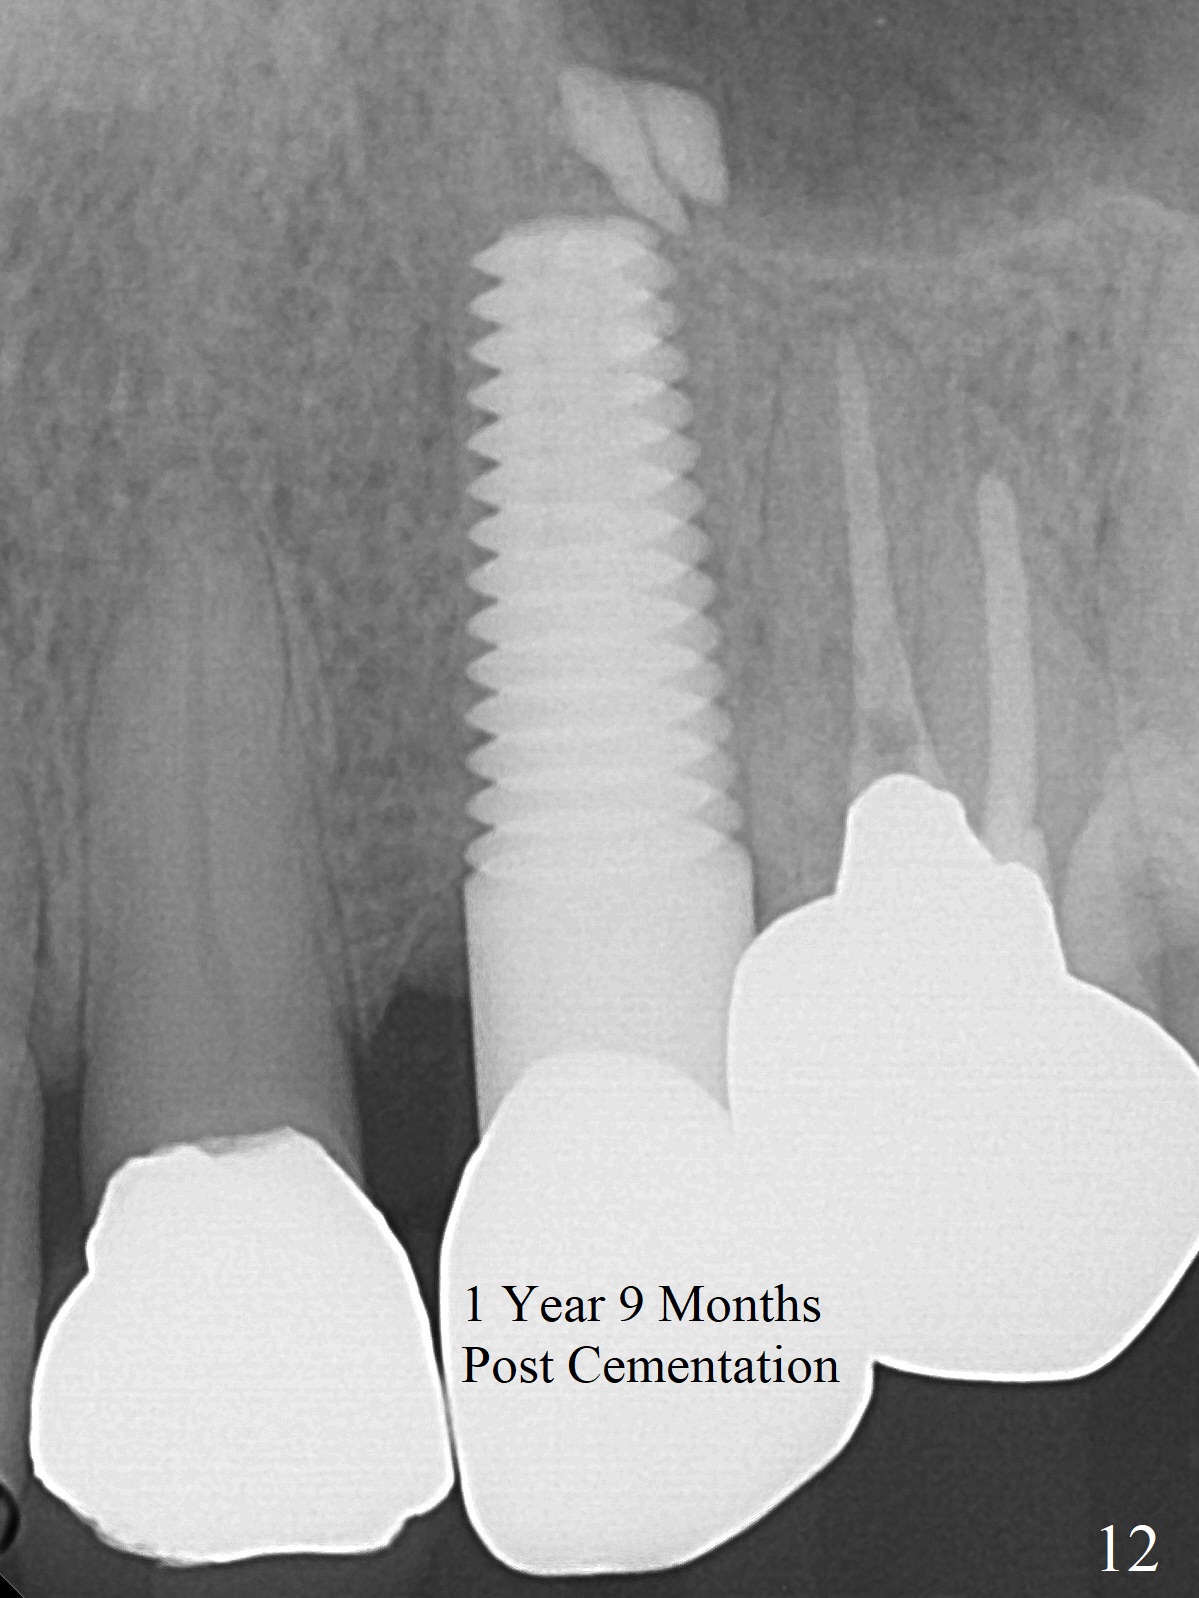

Extraction of the residual root at #11 (Fig.1) turns out to be difficult (Fig.2 (arrow: after use of small elevator). The tooth is sectioned (Fig.2 *); the palatal portion is removed, while the buccal one is trimmed until new moon-shaped and subgingival (Fig.3 * (gauze (G) packed in the socket while photo taking)). Initial osteotomy is 20 mm deep with nasal floor perforation (Fig.4). The subsequent depth is 17 mm (Fig.5). When a 5x17 mm tissue-level implant is placed (Fig.6,7; >60 Ncm), there is a gap between it and the socket shield (Fig.6 *). Gap-filling Vera Graft (Fig.8 *) also covers the shield prior to fabrication of an immediate provisional (Fig.9). There is no apparent bone loss 3.5 months postop (Fig.10). There is no buccal plate resorption 9 months postop (Fig.11). The implant is doing well 2 years postop (1 year 9 months post cementation, Fig.12).